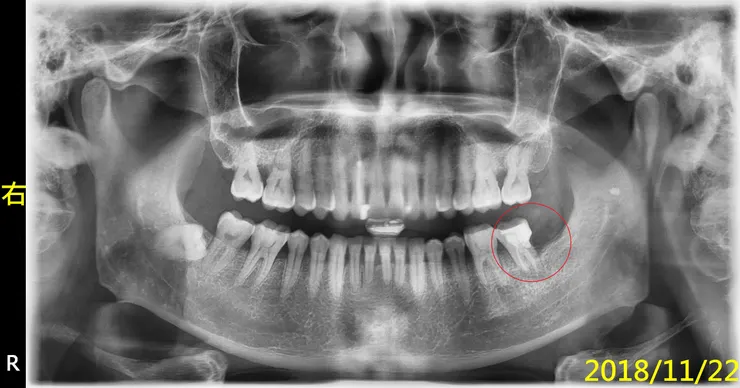

#38智齒拔完後,惡夢還沒結束,還要面對#37的根管治療(抽神經)

一年後,病人回來說,補的掉了

2018時我就已跟病人說的很清楚了,這裡就不贅言,直接引用張添皓醫師的文章說明『根管治療後,不做牙套,是多麼的危險,會導致前功盡棄(保留牙齒廢物利用,不要拔牙)』,何況他的情況,還不能直接做假牙,要先做『牙冠增長術』......所以,為了幫智齒擦屁股、收拾爛攤子,您看事後要付出多大的代價....